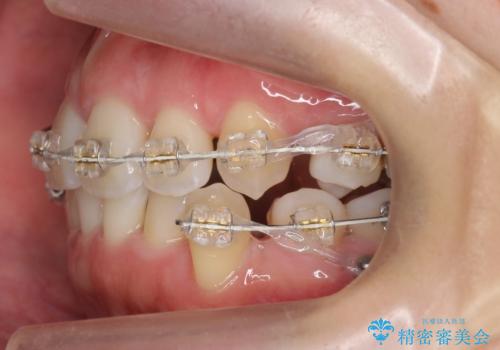

- 矯正装置

- 審美装置

- 治療期間

- 2年3ヶ月

- 治療回数

- 10-30回

- 前歯のがたつきと正中のずれを主訴に来院。

小臼歯を4本抜歯しています。

ワイヤー矯正は時間はかかりますが、仕上がった後の自然な美しさは他の追随を許しません。